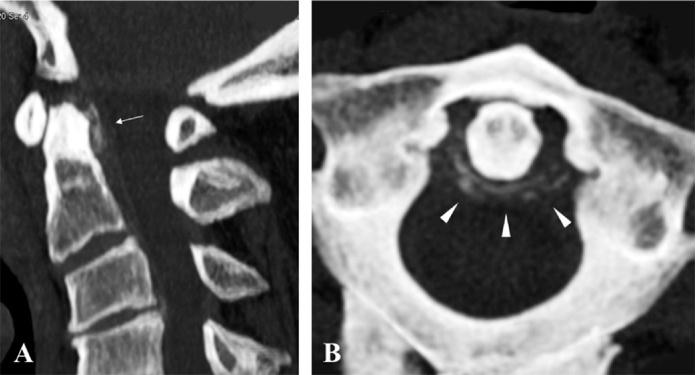

A 61-year-old man was admitted to our hospital with a severe occipital headache and sudden onset of neck stiffness. Neurological examination on admission revealed a high fever and cervical rigidity. Laboratory examination revealed a markedly elevated white blood cell count and C-reactive protein level, but cerebrospinal fluid studies revealed only a slight abnormality. A cervical computed tomography scan and its three-dimensional reconstruction detected a remarkable crown-like calcification surrounding the odontoid process. Cervical magnetic resonance imaging did not demonstrate strong direct compression of the cervical cord; however, the soft tissue surrounding the odontoid process was hyperintense on T2-weighted imaging with fat suppression. Based on the radiological findings, the patient was diagnosed with crowned dens syndrome and was immediately treated with non-steroidal anti-inflammatory drugs. The patient's condition drastically improved within 5days.

一名61岁男性因严重枕部头痛和突然出现的颈部僵硬入住我院。入院时神经系统检查发现高热和颈部强直。实验室检查显示白细胞计数和C反应蛋白水平明显升高,但脑脊液检查仅显示轻微异常。颈椎计算机断层扫描及其三维重建检测到齿状突周围有明显的冠状钙化。颈椎磁共振成像未显示脊髓有强烈的直接压迫;然而,在脂肪抑制T2加权成像上,齿状突周围的软组织呈高信号。根据放射学检查结果,该患者被诊断为齿状突冠综合征,并立即接受非甾体抗炎药治疗。患者的病情在5天内大幅改善。